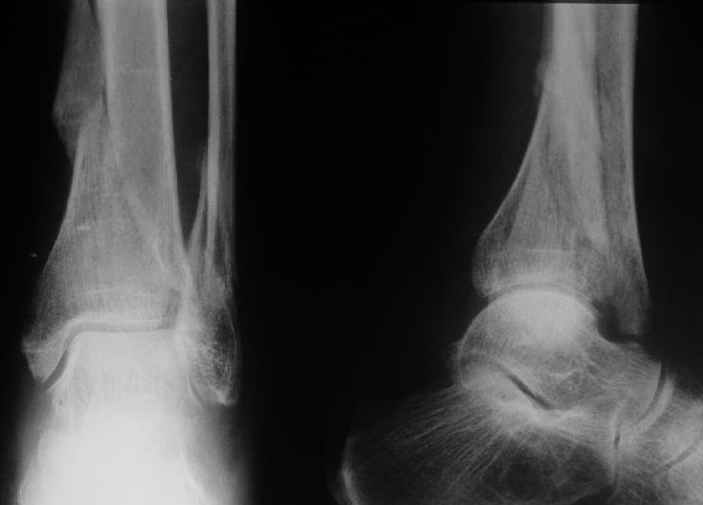

Все-таки ограничились остеотомией этого шипа. Снимок в приложении.

Кликните для загрузки файла get_image.jpg

Отправитель: Андрей 30 Август 2004, 00:44

Судя по рентгену, там вполне приличное сращение.Ось сохранена, укорочение - макс. 1,5 см. Чего ещё хотеть? Шип желатепьно убрать. Исключительно, чтобы

улучшить Rtg-картинку и обезопасить больную от энтузиастов с горячими руками.

Though the upper tibia is not seen on the Xray and thus we cannot exactly see the amount of varus angulation, I presume it must be minimal and acceptable, otherwise you have noted and mentioned the same.